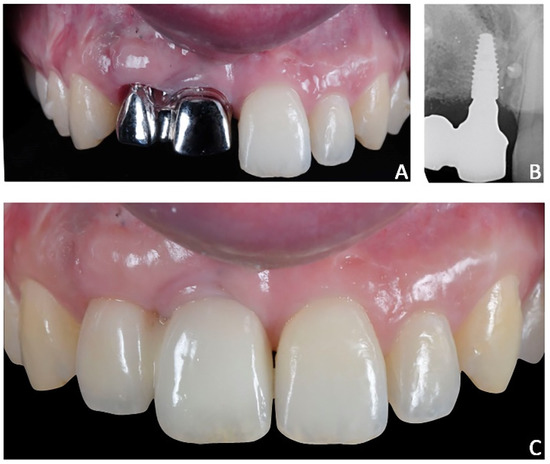

A 24-year-old female attended a consultation for prosthetic treatment after several treatment failures. Her chief complaint was to enhance the smile’s aesthetic and possibly receive a fixed prosthesis without involving natural teeth. The patient previously underwent endodontic treatment of 1.1 and 1.2 after a traumatic injury in childhood. Subsequently, the same elements were treated with endodontic surgery and extracted after repeated abscess episodes. The last treatment, performed in adulthood, consisted of bone reconstruction by using a bone block graft to provide structural support to the anterior segment and for implant placement; however, even this solution failed, as confirmed by the exposure of the fixing screw and the inflamed surrounding tissues. The patient wore a Maryland with fiberglass and resin teeth that was repaired several times and interfered with proper maneuvers of oral hygiene (Figure 8A).

The first part of the therapy consisted of removing the causes of inflammation in the anterior segment, respectively, in the edentulous area removing the fixing screw and around natural teeth by performing professional oral hygiene and scaling (Figure 8B). After that, the treatment plan for implant-prosthetic rehabilitation of the 2.1 was performed and supported by digital systems:

• Prosthetically guided implant planning. After removing the provisional prosthesis, an intra-oral scan was recorded, and the lab technician was asked to produce a virtual wax-up of the ideal position of the teeth. A Cone-Beam Computed Tomography (CBCT) was performed, and the 3D rendered model of the maxilla was registered with the intra-oral scan using the implant planning software Co-Diagnostix (Straumann, Montreal, Canada) (Figure 9). The software was used to plan the implant’s ideal position and design a surgery guide. Figure 10 shows the clinical procedure of the guided implant surgery. Once the osseointegration occurred, an intra-oral scan was performed to register the position of the implant and the surrounding soft tissues with the healing abutment in place (Figure 11A,B).

Figure 8. Case 2. Pre-treatment condition. (A) Maryland with fiberglass and resin teeth, repaired several times and interfering with proper maneuvers of oral hygiene; (B) absence of soft-tissue inflammation after oral hygiene and scaling.

Figure 11. Case 2. (A) Healing abutment; (B) intra-oral scan with scan-body to detect the axial orientation of the implant; (C) prosthetic restoration.

Figure 14. Case 2. Final prosthesis using milled cobalt-chrome structure and feldspathic porcelain. (A) Milled cobalt-chrome structure; (B) radiographic evaluation; (C) prosthesis veneered with feldspathic porcelain.